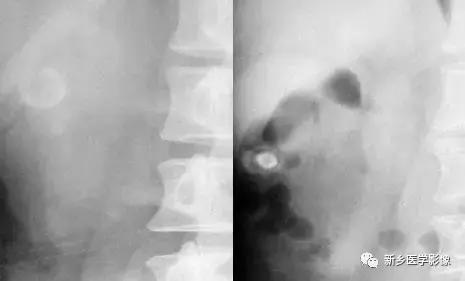

尿路结石

常见于尿路阳性结石,可以发生在尿路任何位置,如肾结石、输尿管结石及膀胱结石